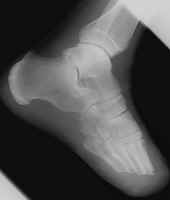

Another transmetatarsal amputation.